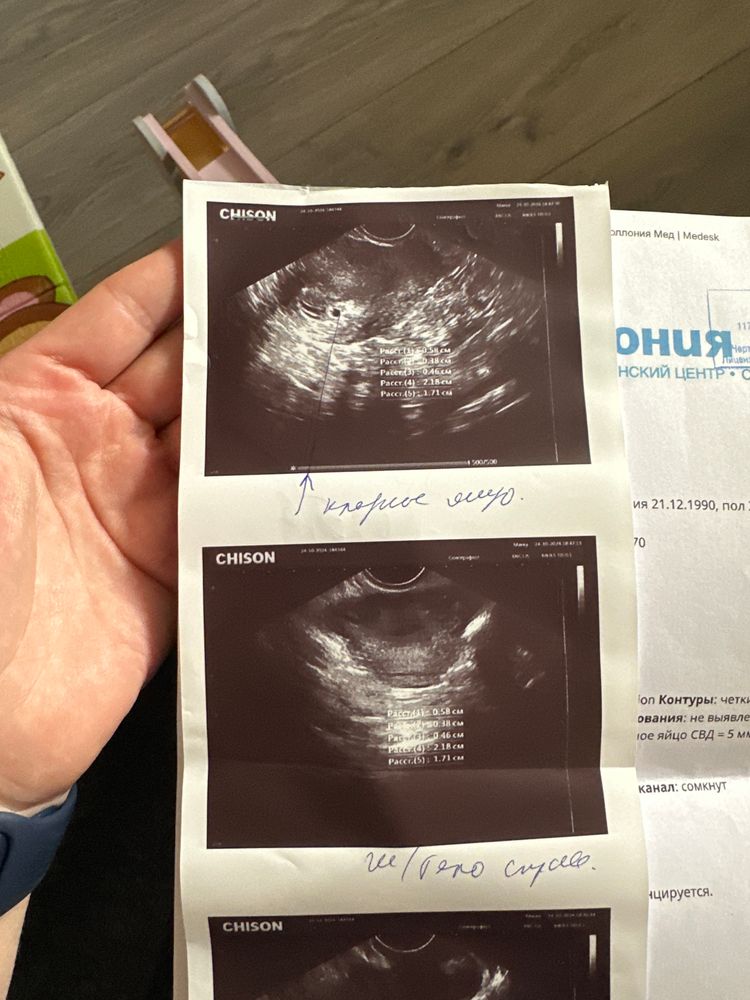

Можете скинуть свое узи?

Татьяна Демкина, жёлтое тело прекрасное, соответствует норме при беременности. Не волнуйтесь, оно обычно во время беременности не растёт.